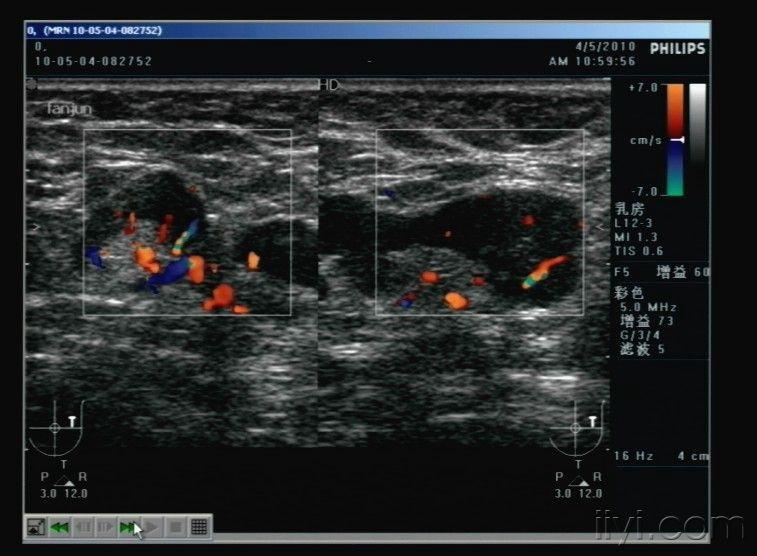

乳腺结节,就是乳腺发生病变,一般包括乳腺增生、乳腺纤维瘤、浆细胞性乳腺炎、乳腺癌等。现在乳腺癌发病率高,内因与乳腺发现结节有很大的关系。